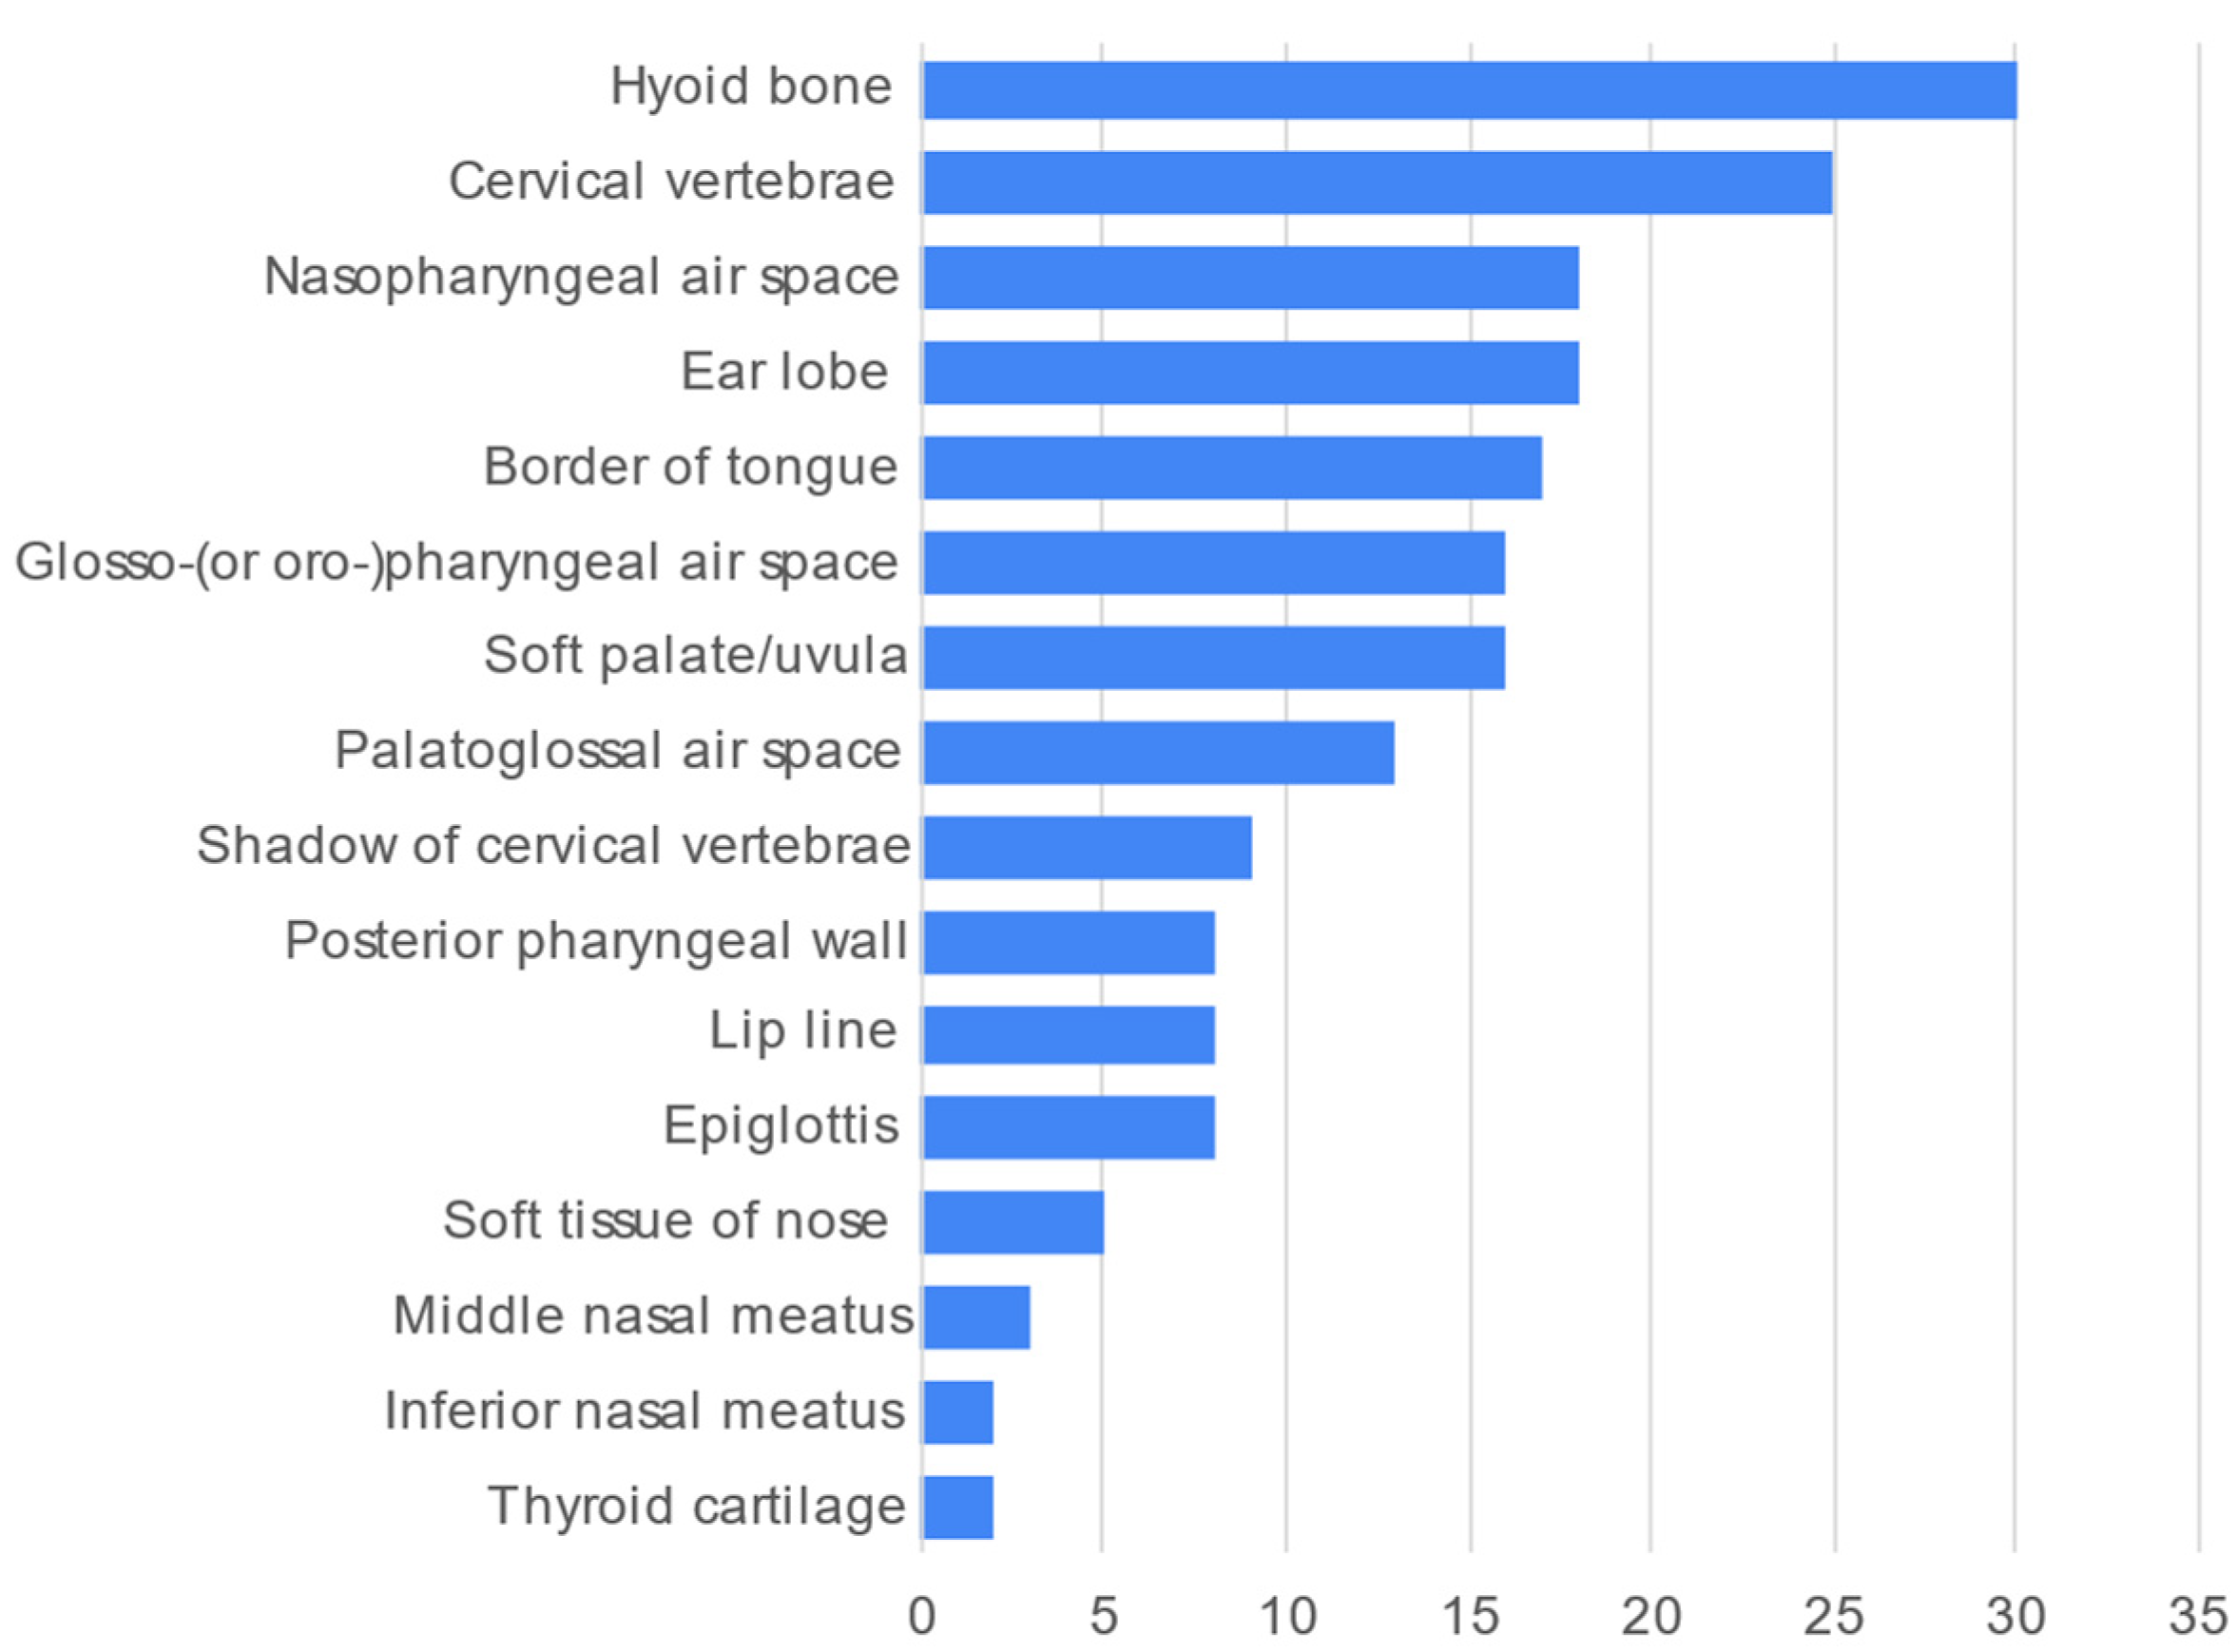

3. Results

| Soft tissues/air spaces/others | ||

| Soft tissues/air spaces/others | ||

| Soft tissue/air space/others | 5.2 ± 3.9 | 0; 15 |